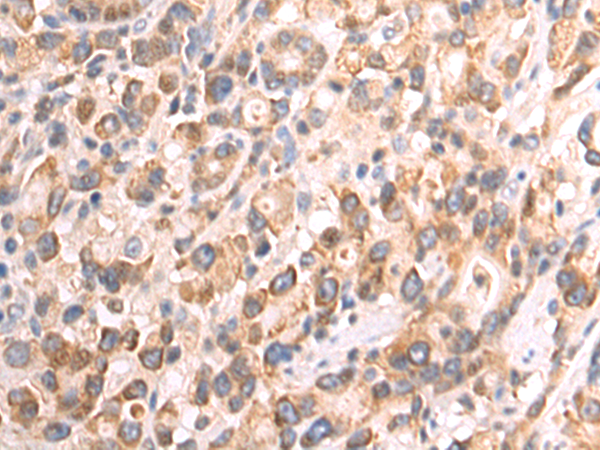

分类: 科研抗体货号: P07218别名: COX11P应用: WB,IHC反应种属: Human, Mouse